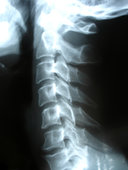

Oriental Medicine can be a fabulous way to treat soft-tissue injury resulting from motor vehicle and other accidents. A combination of acupuncture, cupping, electroacupuncture, Chinese herbs, and/or moxibustion can help to relieve your pain, decrease inflammation, improve your response to physical therapy, and improve healing time.